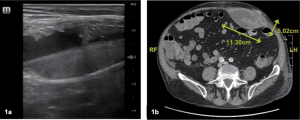

A 59-year-old man with past medical history including obesity status post gastric banding surgery and atrial fibrillation on rivaroxaban, presented to the emergency department with a complaint of focal pain to his right abdomen along with areas of visible bruising. He noted that since his diagnosis of COVID-19 a week prior, he had been having paroxysms of coughing. During one episode of coughing a few days prior to seeking medical care, the patient recalled a “ripping” sensation in his right abdomen followed by intermittent achiness and bruising to that area. The patient reported that his pain worsened with certain movements and coughing but he could tolerate food and liquids without any issues. Although his ecchymosis was scattered across his abdomen on exam, he elicited focal tenderness in his right upper quadrant (Figure 1). The assessing medical provider placed an ultrasound probe directly over the area of pain which revealed a hypoechoic, ovoid hematoma adjacent to the rectus sheath (Figure 2). As the patient was taking rivaroxaban, a CT was obtained to rule out active extravasation. CT confirmed the finding of rectus sheath hematoma without acute bleeding (Figure 3). A complete blood count revealed a normal hemoglobin. Liver function tests, lipase, lactic acid and basic metabolic panel were also within normal limits. The patient was subsequently discharged home with instructions to apply intermittent ice to his abdomen, hold his rivaroxaban for two days, and follow up with his primary care physician in three days.

Figure 2. POCUS finding of rectus sheath hematoma. Hypoechoic hematoma (red arrow) deep to the hyperechoic aponeurosis of the anterior rectus sheath.

Figure 3. Transverse cut of CT imaging revealing right abdominal wall hematoma (red arrow) that was measured to be approximately 11.4 x 2.6 x 8.4cm in volume.